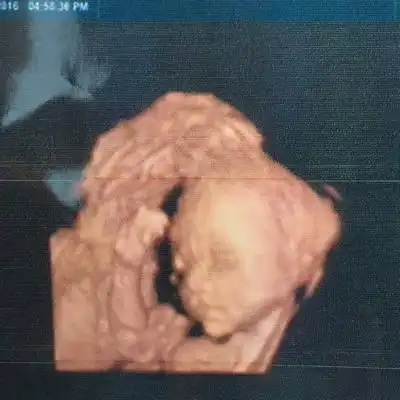

前两天做的四维,四维图上看起来正常,可是放大的照片看起来像兔唇,问

四维查出胎儿唇裂,为所有孕妈敲响警钟!

双胎宝妈21周做四维彩超筛查出一名胎儿为唇腭裂

书摘笔记胎儿唇腭裂的超声诊断

我怀疑我的宝宝是兔唇,我好担心我该怎么办

为孕妇敲警钟二胎忽视产检孕晚期却查出胎儿唇腭裂